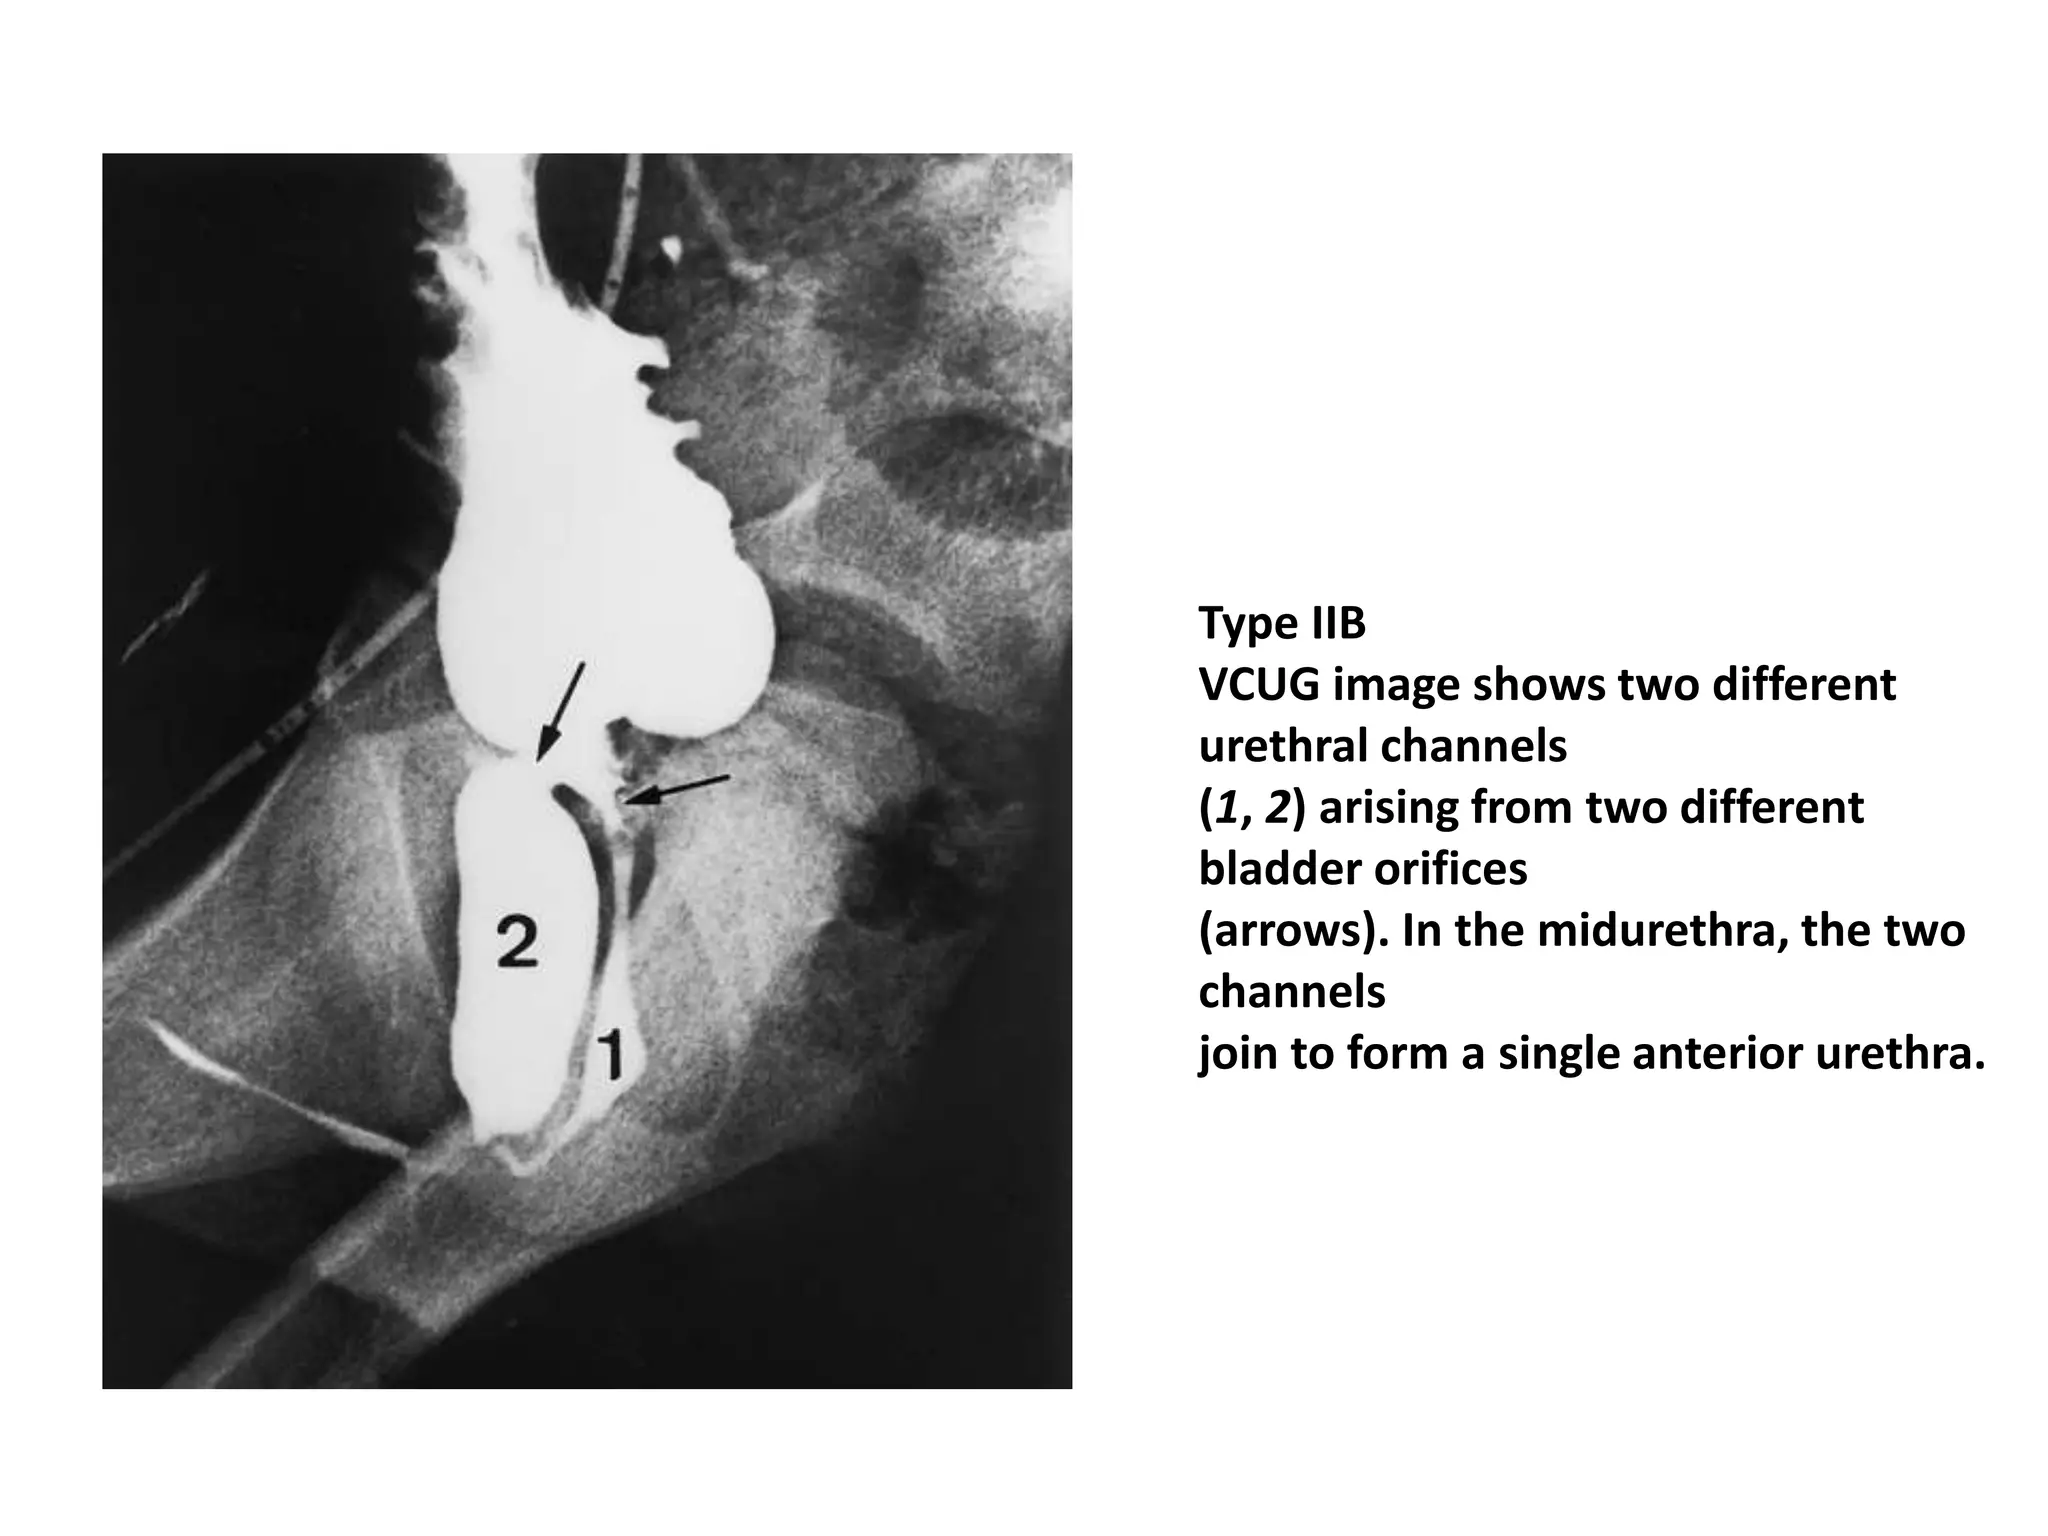

Type IIB

VCUG image shows two different

urethral channels

(1, 2) arising from two different

bladder orifices

(arrows). In the midurethra, the two

channels

join to form a single anterior urethra.

Type IIB VCUG imageshows two different urethral channels (1, 2) arising from two different bladder orifices (arrows). In the midurethra, the two channels join to form a single anterior urethra.